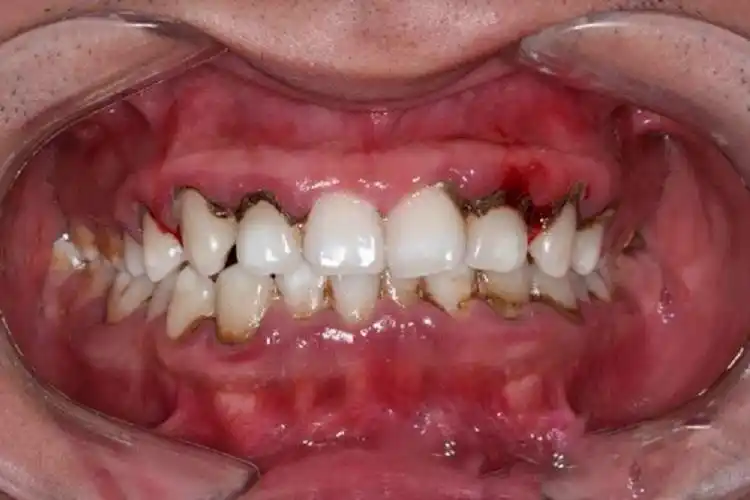

牙周炎图片_牙周炎症状表现图片大全_有来医生

牙周炎能治好吗 牙周炎的症状表现大科普!

你知道牙周炎有哪些症状吗?

牙周病的早期症状不明显,不易引起重视,患者常只有激发生性牙龈出血或

牙周炎的早期症状